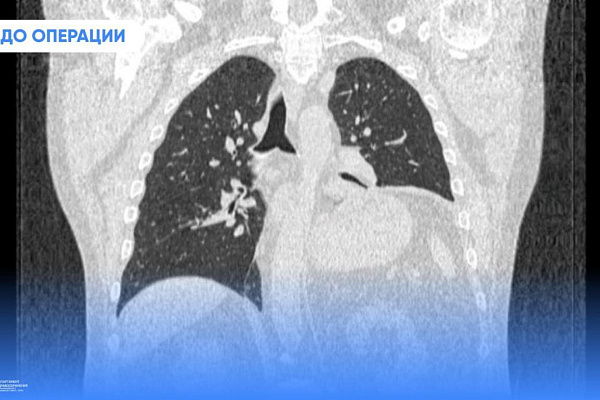

Проблемы со здоровьем сургутянин Юрий Шавров распознал по сильной одышке. Мужчина буквально задыхался при малейших физических нагрузках. Как выяснилось при обследовании, его левое лёгкое значительно уменьшилось в объёме и не может полноценно выполнять свою функцию. И всё потому, что его сдавливает диафрагма.

Расслабленная мышца не способна сопротивляться отрицательному давлению плевральной полости, поэтому под его действием поднимается выше обычного, притесняет лёгкое и не даёт ему расправиться.